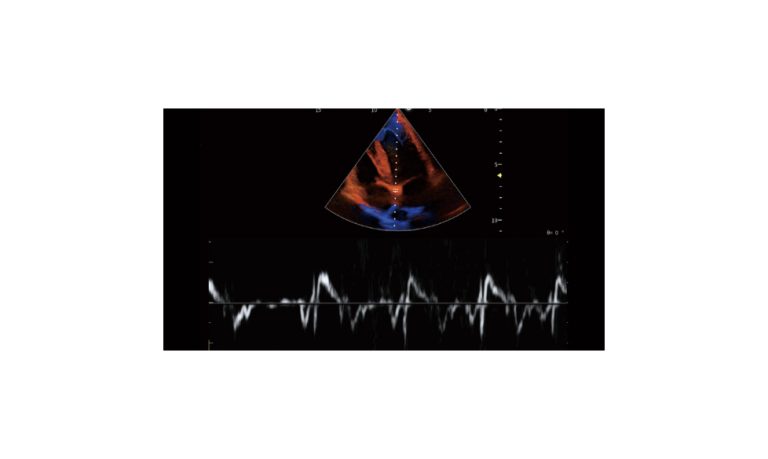

Ultrasound

Wide range of Ultrasound machines that suites a variety of applications from abdominal to rectal scans, we take in consideration how the world is moving towards mobility and mobile applications.

SonoScape Pro Pet E11

Smart Imaging

Introducing the first portable ultrasound with the C-Field+TM platform, redefining diagnostic imaging. Designed for veterinarians, it delivers unmatched clarity, ultra-fast processing, and seamless adaptability for all species. Experience Smart Imaging, Heartfelt Care—anywhere.

Equipped with cutting-edge veterinary software and optimized workflows, it embodies our commitment to Smart Imaging, Heartfelt Care – Wherever Their Journey Leads, with unparalleled performance and adaptability, this innovative system empowers veterinarians to provide exceptional care across all diagnostic applications,

EBIT50/60 VET

All the power you need

The EBit provides all the power you need for today´s challenging clinical environment, yet remain ultra-portable, ultra-affordable. With its cutting-edge imaging technologies, precise and intuitive workflow, ergonomic and eco-friendly design, versatile transducers for all applications from top to toe, we firmly believe the EBit to be the very best portable ultrasound in its class today.

ECO5 VET

Ultra-Portable, Ultra- Affordable, Color doppler

The multi-purpose user presets, comprehensive measurement & report system, built-in EasyView image achieve system, quick image storage / retrieve / transfer, one-button direct print, make the complete workflow better than what you can dream of.